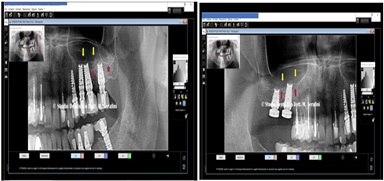

Control at six months on the right side and at 14 months on the left side, after finalization (Figure 27).

Figure 27: Control at six months on the right side and at 14 months on the left side.

Rx details in figure 28.

Figure 28: Left Side and Right Side note: the red arrows were the old sinus pavment and the yellow arrows, the new sinus pavment.